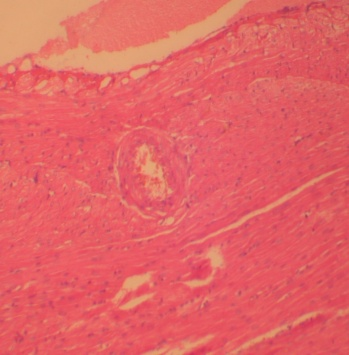

Histopathological studies

After 6 w, rats were anesthetized; blood was withdrawn by the retro-orbital method and serum was obtained by centrifugation. Post blood withdrawal rats were sacrificed, organs like heart, liver, kidney and tissues like perirenal, epididymal and mesenteric fat pads were excised immediately, rinsed with phosphate buffer saline and weighed. The samples were stored at-70 °C and were given for histopathological studies [21].

P. nigrum treated group (HFD+PN): Hepatocytes

Standard group: No fat deposition

P. nigrum per se group: Hepatocytes

Fig. 3: Changes observed in the liver of different groups

Histopathological examination of liver, heart and kidney revealed that the rats treated with test extract (P. nigrum) showed a marked reduction in the accumulation of fats in the liver, heart and kidney.